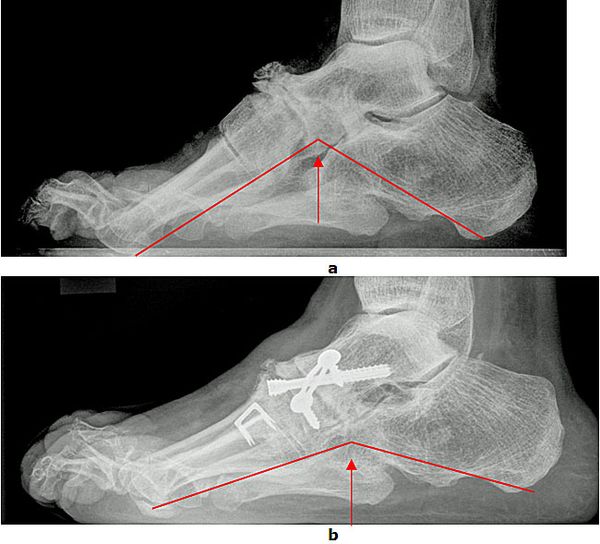

Abb.7: a Erhöhte Fußwölbung und Spitzfußstellung vor der Operation. b Wiederherstellung der Fußform postoperativ

Trotz erheblicher Fehlstellungen können Patienten mit geringen Beschwerden zunächst mit speziellen Einlagen (Stufeneinlage) und/oder orthopädischen Schuhen versorgt werden. Bei starken Beschwerden bedarf es einer operativen Korrektur des Fußes. Die Hohlfußdeformität wird am Scheitelpunkt der Fehlstellung durch die Entnahme eines Knochenkeils korrigiert. Liegt eine zusätzliche Steilstellung des ersten Strahls vor folgt eine zusätzliche Keilentnahme an der Basis des ersten Mittelfußknochens. Durch Eingriffe an den Sehnen werden die Krallenzehen behandelt und die muskuläre Balance des Fußes wieder hergestellt.

Abb.8: a Wiederherstellung der Fußwölbung vor und

b nach der Operation im seitlichen Röntgenbild